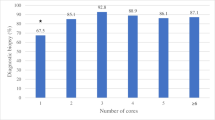

Details pertaining to lesion-related and technical factors are summarized in Table 1. Overall diagnostic yield was 98.2%, with 2279 of 2321 biopsies yielding a sufficient histopathologic diagnosis. In multivariate statistical analysis, increased total core length (odds ratio [OR] = 2.34, 95% CI (1.41–3.90), p = 0.001), core number (OR = 1.51, 95% CI (1.06–2.16), p = 0.02), and presence of primary malignancy (OR = 2.81, 95% CI (1.40–5.62), p = 0.004) were found to be associated with improved yield. Lesion location in an extremity (OR = 0.27, 95% CI (0.11–0.68), p = 0.006) and using fluoroscopic imaging guidance (OR = 0.33, 95% CI (0.12–0.90), p = 0.03) were found to be associated with lower yield. See Table 2 for univariate statistical analysis and Table 3 for multivariate statistical analysis of the factors selected after backward stepwise selection. The cutoff at which increased total core length reached a threshold value in relation to increased diagnostic yield was found to be 20 mm (marginal OR = 4.16, 95% CI = (2.09–9.03), p < 0.001) with corresponding box plot and contingency table shown in Fig. 3. The cutoff at which increased core number reached a threshold value in relation to increased yield was found to be 3 total cores obtained (marginal OR = 2.78, 95% CI (1.34–6.54, p = 0.005) with corresponding box plot and contingency table shown in Fig. 4. Marginal odds ratios of different tested cutoff values for total core length and number of cores can be seen in Table 4, and the values in this table for total core length are represented graphically in Fig. 5. The most common histopathological diagnoses of malignant lesions can be seen in supplemental Table 1 (electronic supplemental material).

a Boxplot displaying the total number of cores obtained from diagnostic and non-diagnostic biopsies, with three core cutoffs shown as a horizontal line on the box plot. b 2 x 2 contingency table compares diagnostic and non-diagnostic biopsies with biopsies above and below the three-core cutoff. Marginal odds ratio shown below table

While our study has shown that increased lesion sampling via increased core number and total core length increases diagnostic yield, increased sampling ostensibly also increases procedure time and might increase the potential for complications, sedation, and exposure to ionizing radiation. Thus, obtaining threshold values for the core number and total core length at which diagnostic yield plateaus is important. The only study in the literature that has focused on optimizing technical parameters for bone biopsy (to our knowledge) has been the study by J Wu et al, who in an analysis of 88 bone biopsies, reported that diagnostic yield reached a plateau at three total cores obtained [5]. Our current study of 2321 biopsies has replicated this finding. Additionally (to our knowledge), no other studies in the literature have investigated the total core length that optimizes diagnostic yield. We found that the relationship between increased total core length and increased yield starts to plateau at 20 mm. Thus, we recommend that for bone biopsies of suspected malignant lesions, operators should attempt to obtain three cores and 20 mm total core length to optimize diagnostic yield.